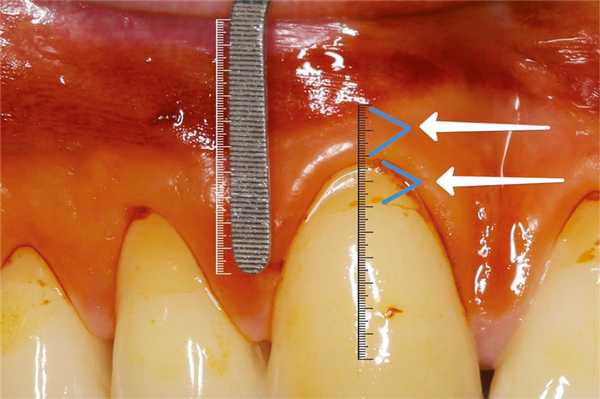

В большинстве случаев при определении таких клинических параметров, как высота КД и глубина рецессии, исследователи используют градуированный зонд или штангенциркули Кастровьехо с разрешающей способностью от 0,5 до 1 мм. Мы использовали стоматологическую гладилку, на которую нанесли лазерную насечку (рис. 2), Рис. 2. Масштабирование фотографий и расчет показателей высоты КД и величины рецессии. имеющую шаг 0,2 мм (200 мк), в целях повышения точности исследования. Глаз человека как естественный оптический прибор имеет определенную разрешающую способность [19], но работа с такими малыми величинами имеет значительную погрешность, поэтому для измерения мы использовали следующую методику: после окрашивания десны раствором Шиллера рядом с исследуемым участком прикладывали стоматологическую гладилку с лазерной насечкой. После фотографирования объекта в режиме макросъемки и масштабирования фотографий проводили расчет и фиксировали показатели измерения (рис. 2).

Толщина десны в исследуемой группе была меньше, чем в контрольной: соответственно 0,85 [0,7; 0,95] мм и 0,95 [0,8; 1] мм (см. рис. 3). В группах выявлены достоверные различия (p <0,05). Кроме того, толщина десневого края в обеих группах составляла менее 1 мм и по этому параметру можно считать десну «тонкой» (см. рис. 4). Рис. 4. Измерение толщины десны; использование ретрактора позволяет отодвинуть мягкие ткани губ от альвеолярного отростка.